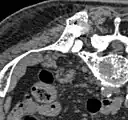

- Vues au scanner d'une ablation aux micro-ondes

Avant l'ablation : crête supérieure arrière de l'ilion, avec une métastase ostéolytique (diam. environ 2 cm, flèches)

A-Pendant l'ablation, l'électrode micro-onde est directement insérée dans la métastase. B-En fin d'ablation, un mélange de ciment pour os et de sulfate de baryum est injecté dans l'espace vide créé.

Après ablation, la répartition du ciment dans l'espace vide est visible.